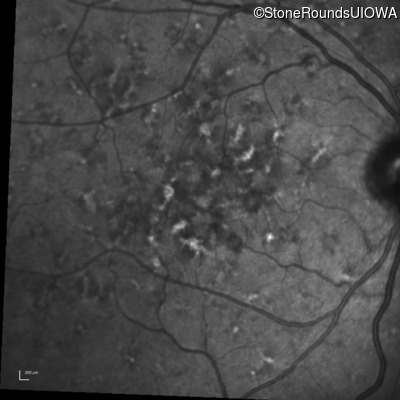

Fluorescein Angiography - Right - 20/40 +2 sc

Exemplar